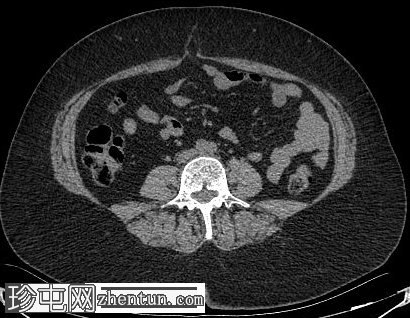

轴位增强扫描

门静脉期

肝脏内可见多发边界清晰的脂肪结节状病变,最大病变位于肝脏VII段,直径15 mm

双肾可见多发脂肪肿块,右肾最大病变直径达45 mm,左肾最大病变直径20 mm

肾脏和肝脏中富含脂肪的血管平滑肌脂肪瘤可能仅有轻微或无明显的对比增强,仅表现为衰减值的轻微升高,反映血管和间质成分的增强。这些病灶内肉眼可见的脂肪具有高度特异性,有助于将血管平滑肌脂肪瘤与其他肾脏和肝脏肿瘤区分开来。

此外,多发性小骨硬化性病变是结节性硬化症的常见骨骼表现,在适当的临床背景下,不应误诊为成骨性转移。